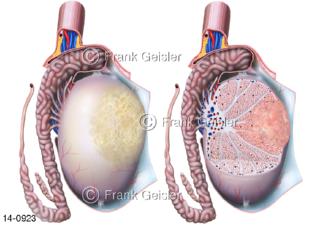

Bildergalerie Urogenitalsystem

Bilder zum Urogenitalsystem mit Urogenitalorgane, Urogenitaltrakt, zum Harn- und Geschlechtsapparat, Harnorgane und Geschlechtsorgane, Organe der Harnwege und der Fortpflanzung, Harnorgane und Geschlechtsorgane im männlichen und weiblichen Urogenitalsystem